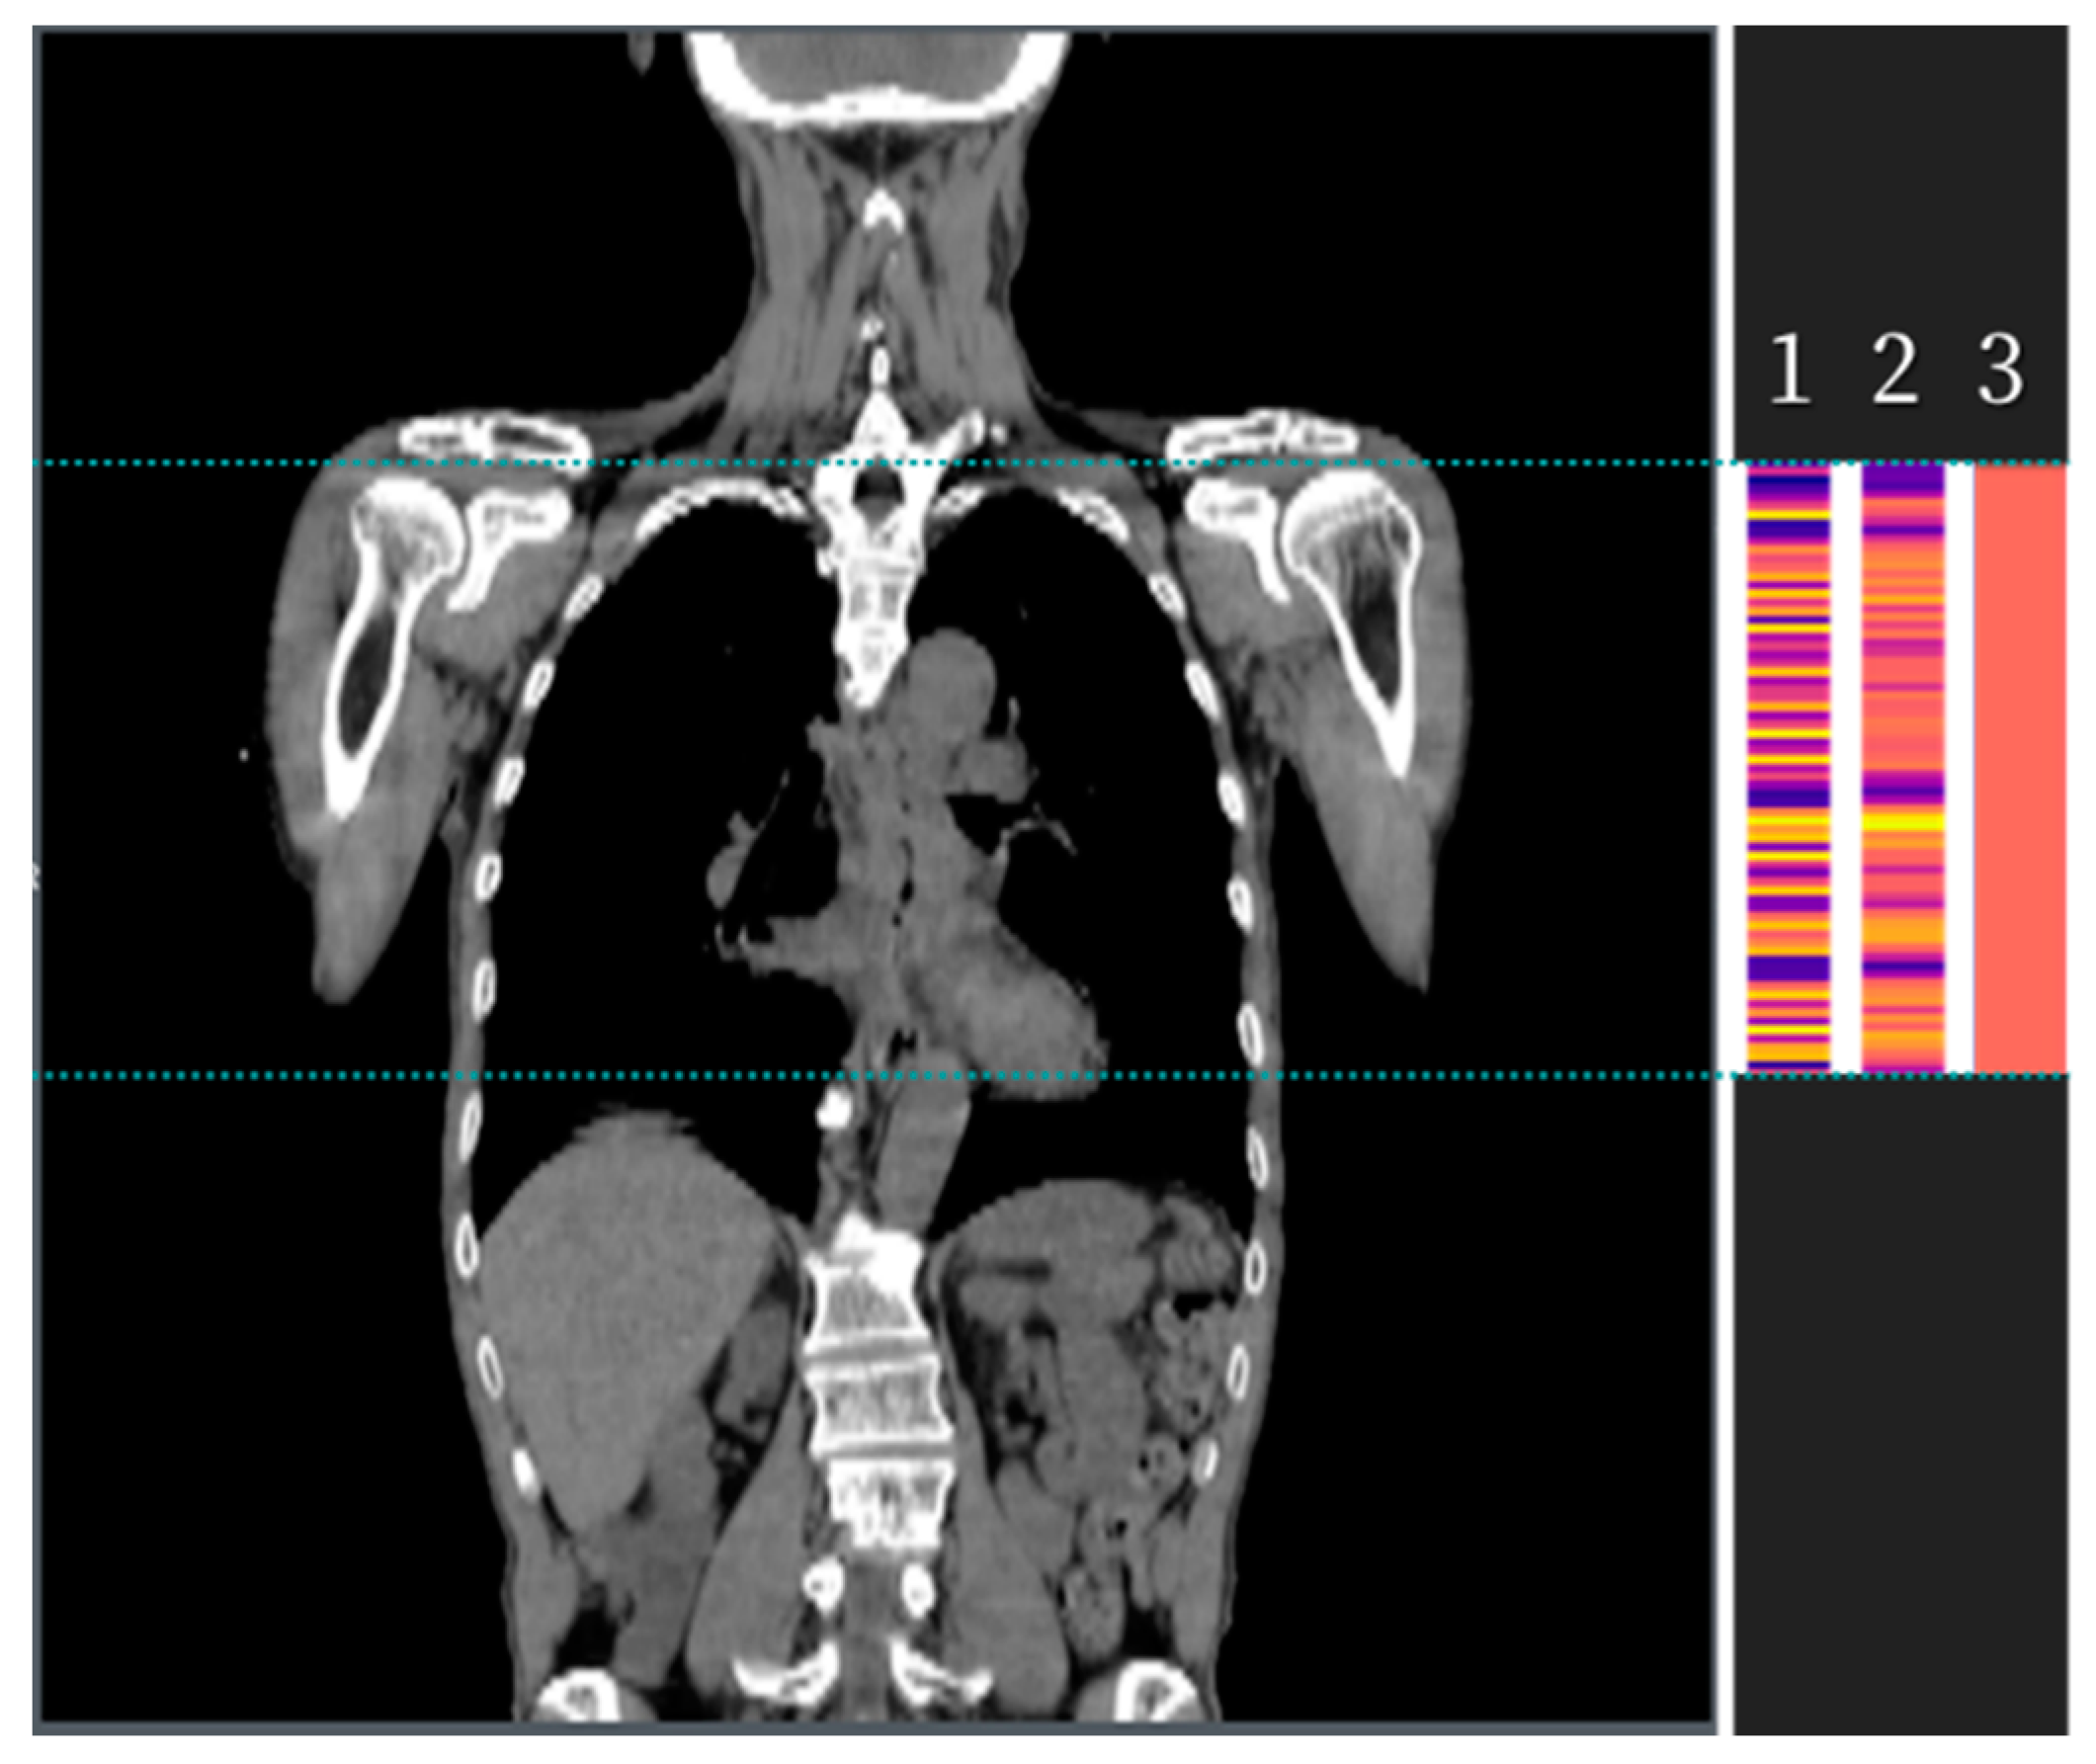

2.2. Development of the Algorithm